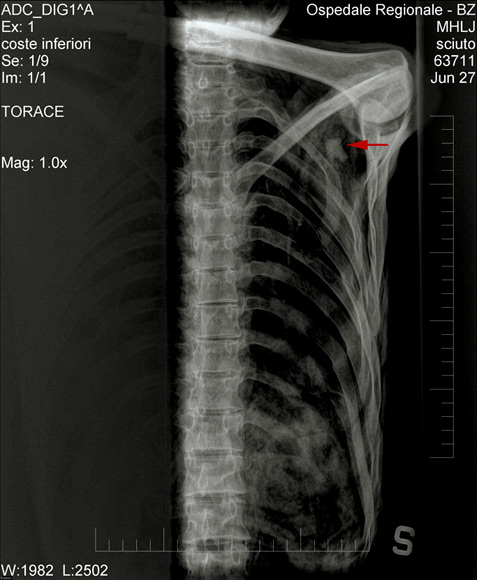

但是尸检表明,奥茨死后被精心安葬。在2001年,科研人员在奥茨肩部发现了一支箭头,科学家据此推断奥茨被人射杀。还有一部分科学家根据奥茨右手和手腕上的刀伤推断奥茨死于持刀打斗。不过这种观点受到了其他科学家的强烈质疑。[page]